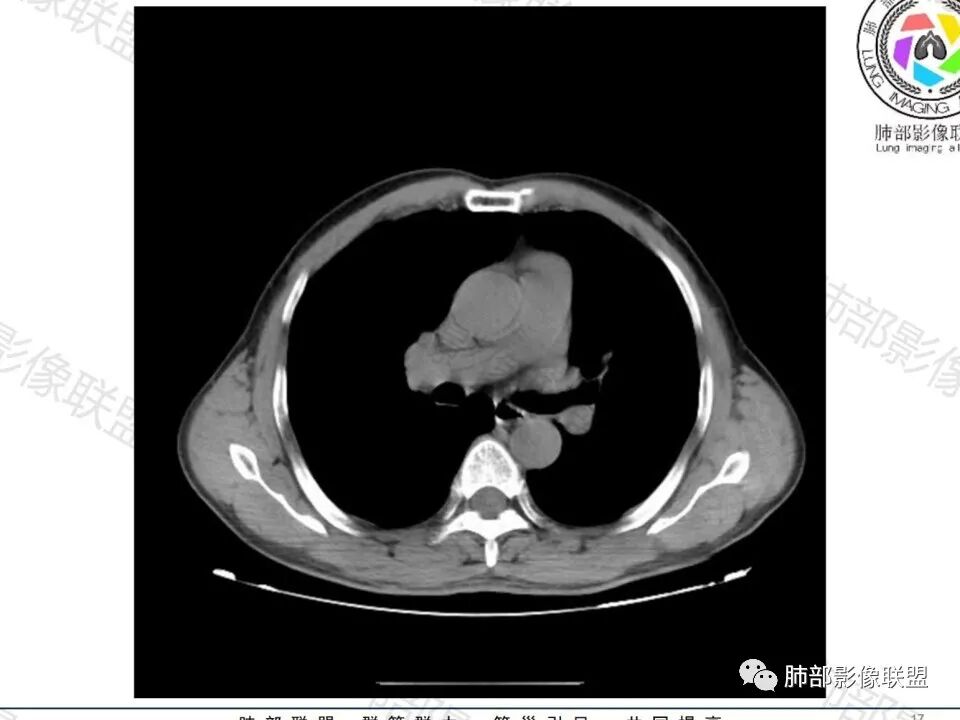

这枚结节的纵隔窗在没有调节窗位的情况下,已经很密实了,说明这个结节里面是软组织的成分,这与普通炎性结节(隐球菌等)的密度还是有区别的,很多年前就有人提出,纵隔窗显示越大,恶性可能越大;

结节周围有磨玻璃影,边界似清不清的,但是总体不如炎性晕征那么模糊;

增强的程度很难讲,但是不均匀强化是可以确定的;

有收缩力,但是很轻,按照常理,实性结节因为有占位效应,不太会有收缩力,但是叶间胸膜有凹陷。所以讲,这个结节还是开了放心。